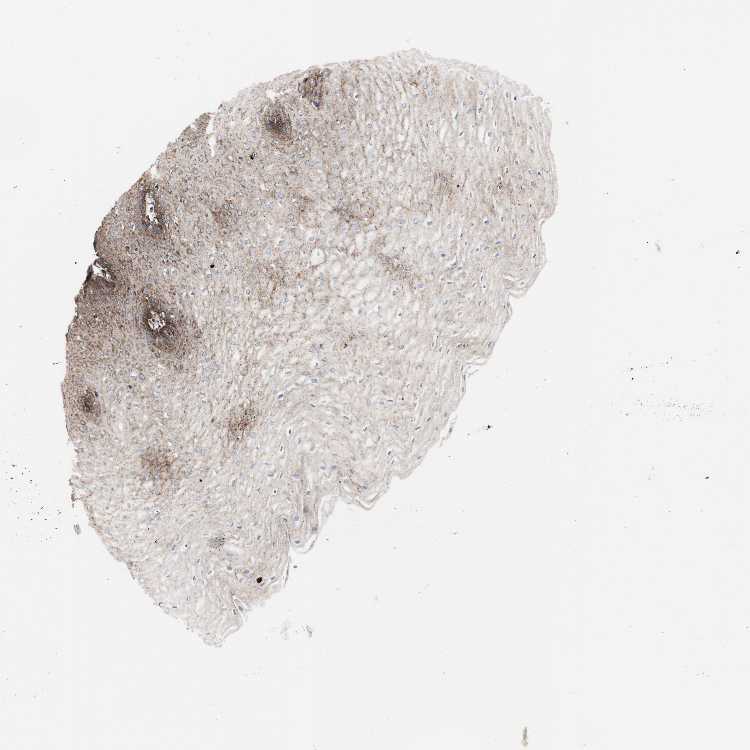

ESOPHAGUS - Antibody stainingi

Antibody staining in the annotated cell types in the current human tissue is reported as not detected, low, medium, or high, based on conventional immunohistochemistry profiling in selected tissues. This score is based on the combination of the staining intensity and fraction of stained cells.

Each image is clickable and will lead to virtual microscopy that enables deeper exploration of all samples and also displays staining intensity scores, fraction scores and subcellular localization as well as patient and tissue information for each sample.

Antibody HPA014750Antibody CAB004260

Squamous epithelial cells LowHigh